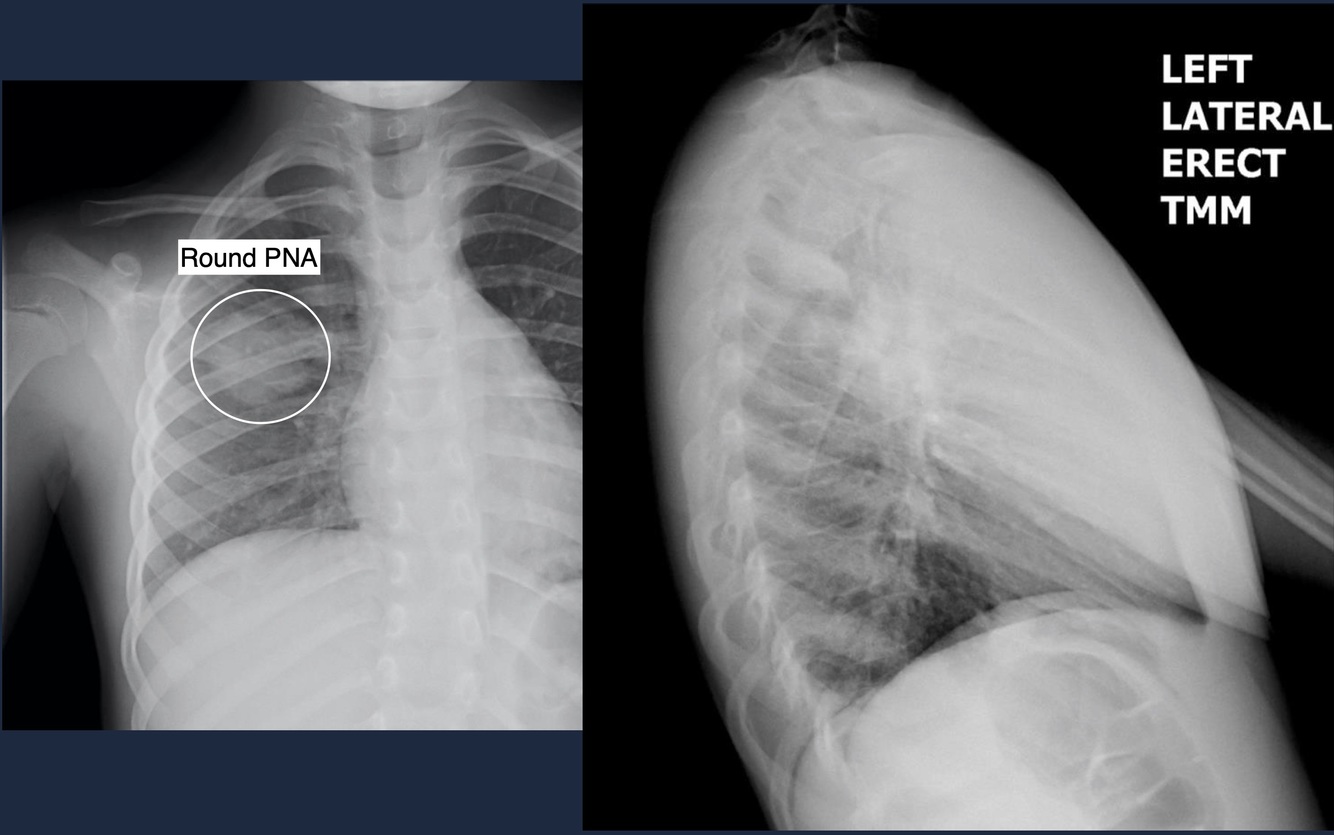

Round Pneumonia

Complications of PNA

Complicated PNA

Work-up

Typically requires cross-sectional imaging:

Ultrasound or CT